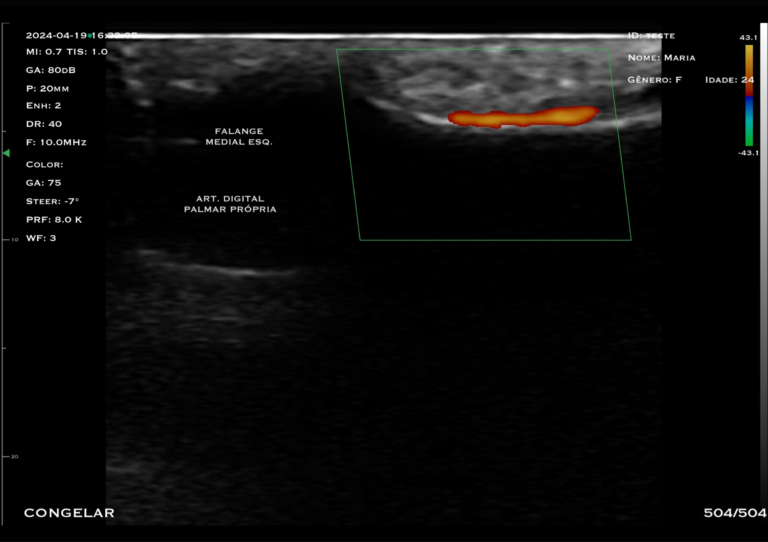

Com tecnologia linear de alta frequência (10 a 14 MHz), o modelo M4D é a escolha ideal para quem busca alta resolução em exames superficiais, com foco em detalhamento e precisão.

O trasdutor linear oferece imagens nítidas e detalhadas, permitindo a visualização precisa de estruturas como pele, tecido subcutâneo, músculos, tendões e articulações.

B, B/M, Color, PDI, PW

Bloqueios de nervos e músculo esquelético, punções superficiais, infiltrações, TAP Block, mensuração de tecido adiposo e entrada de acesso central.